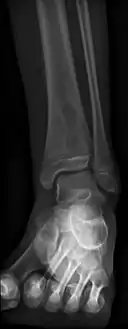

Oval, elliptical, or serpentine radiolucency usually greater than 1 cm surrounded by a heavily reactive sclerosis, granulation tissue, and a nidus often less than 1 cm. The margins often appear scalloped on radiograph. Brodie's abscess is best visualized using computed tomography (CT) scan. Associated atrophy of soft tissue near the site of infection and shortening of the affected bone. Osteoblastoma may be a classic sign for Brodie's abscess.

Periostial reaction along the medial cortex indicates an aggressive lesion. Neoplasm such as Ewing sarcoma and osteomyelitis could both have this plain radiographic appearance. Staphylococcus was recovered at surgery.